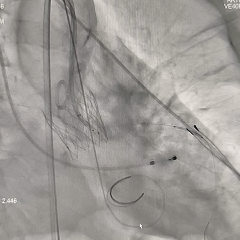

术中影像

左冠提前预埋冠脉导丝

导丝顺利跨瓣

20mm球囊预扩

无腰无漏,右冠显影正常;RN侧钙化融合推挤球囊贴靠左窦侧,可见左冠显影欠佳,考虑有球囊贴靠STJ的原因,决定预埋支架保护再准备瓣膜释放

瓣膜第一次释放

初始定位造影时可见瓣架底端基本平齐猪尾导管(零位),瓣膜释放过程中瓣架出现下滑,至全展开位时瓣膜深度接近一个菱形格,位置过深,即刻回收瓣膜重新调整